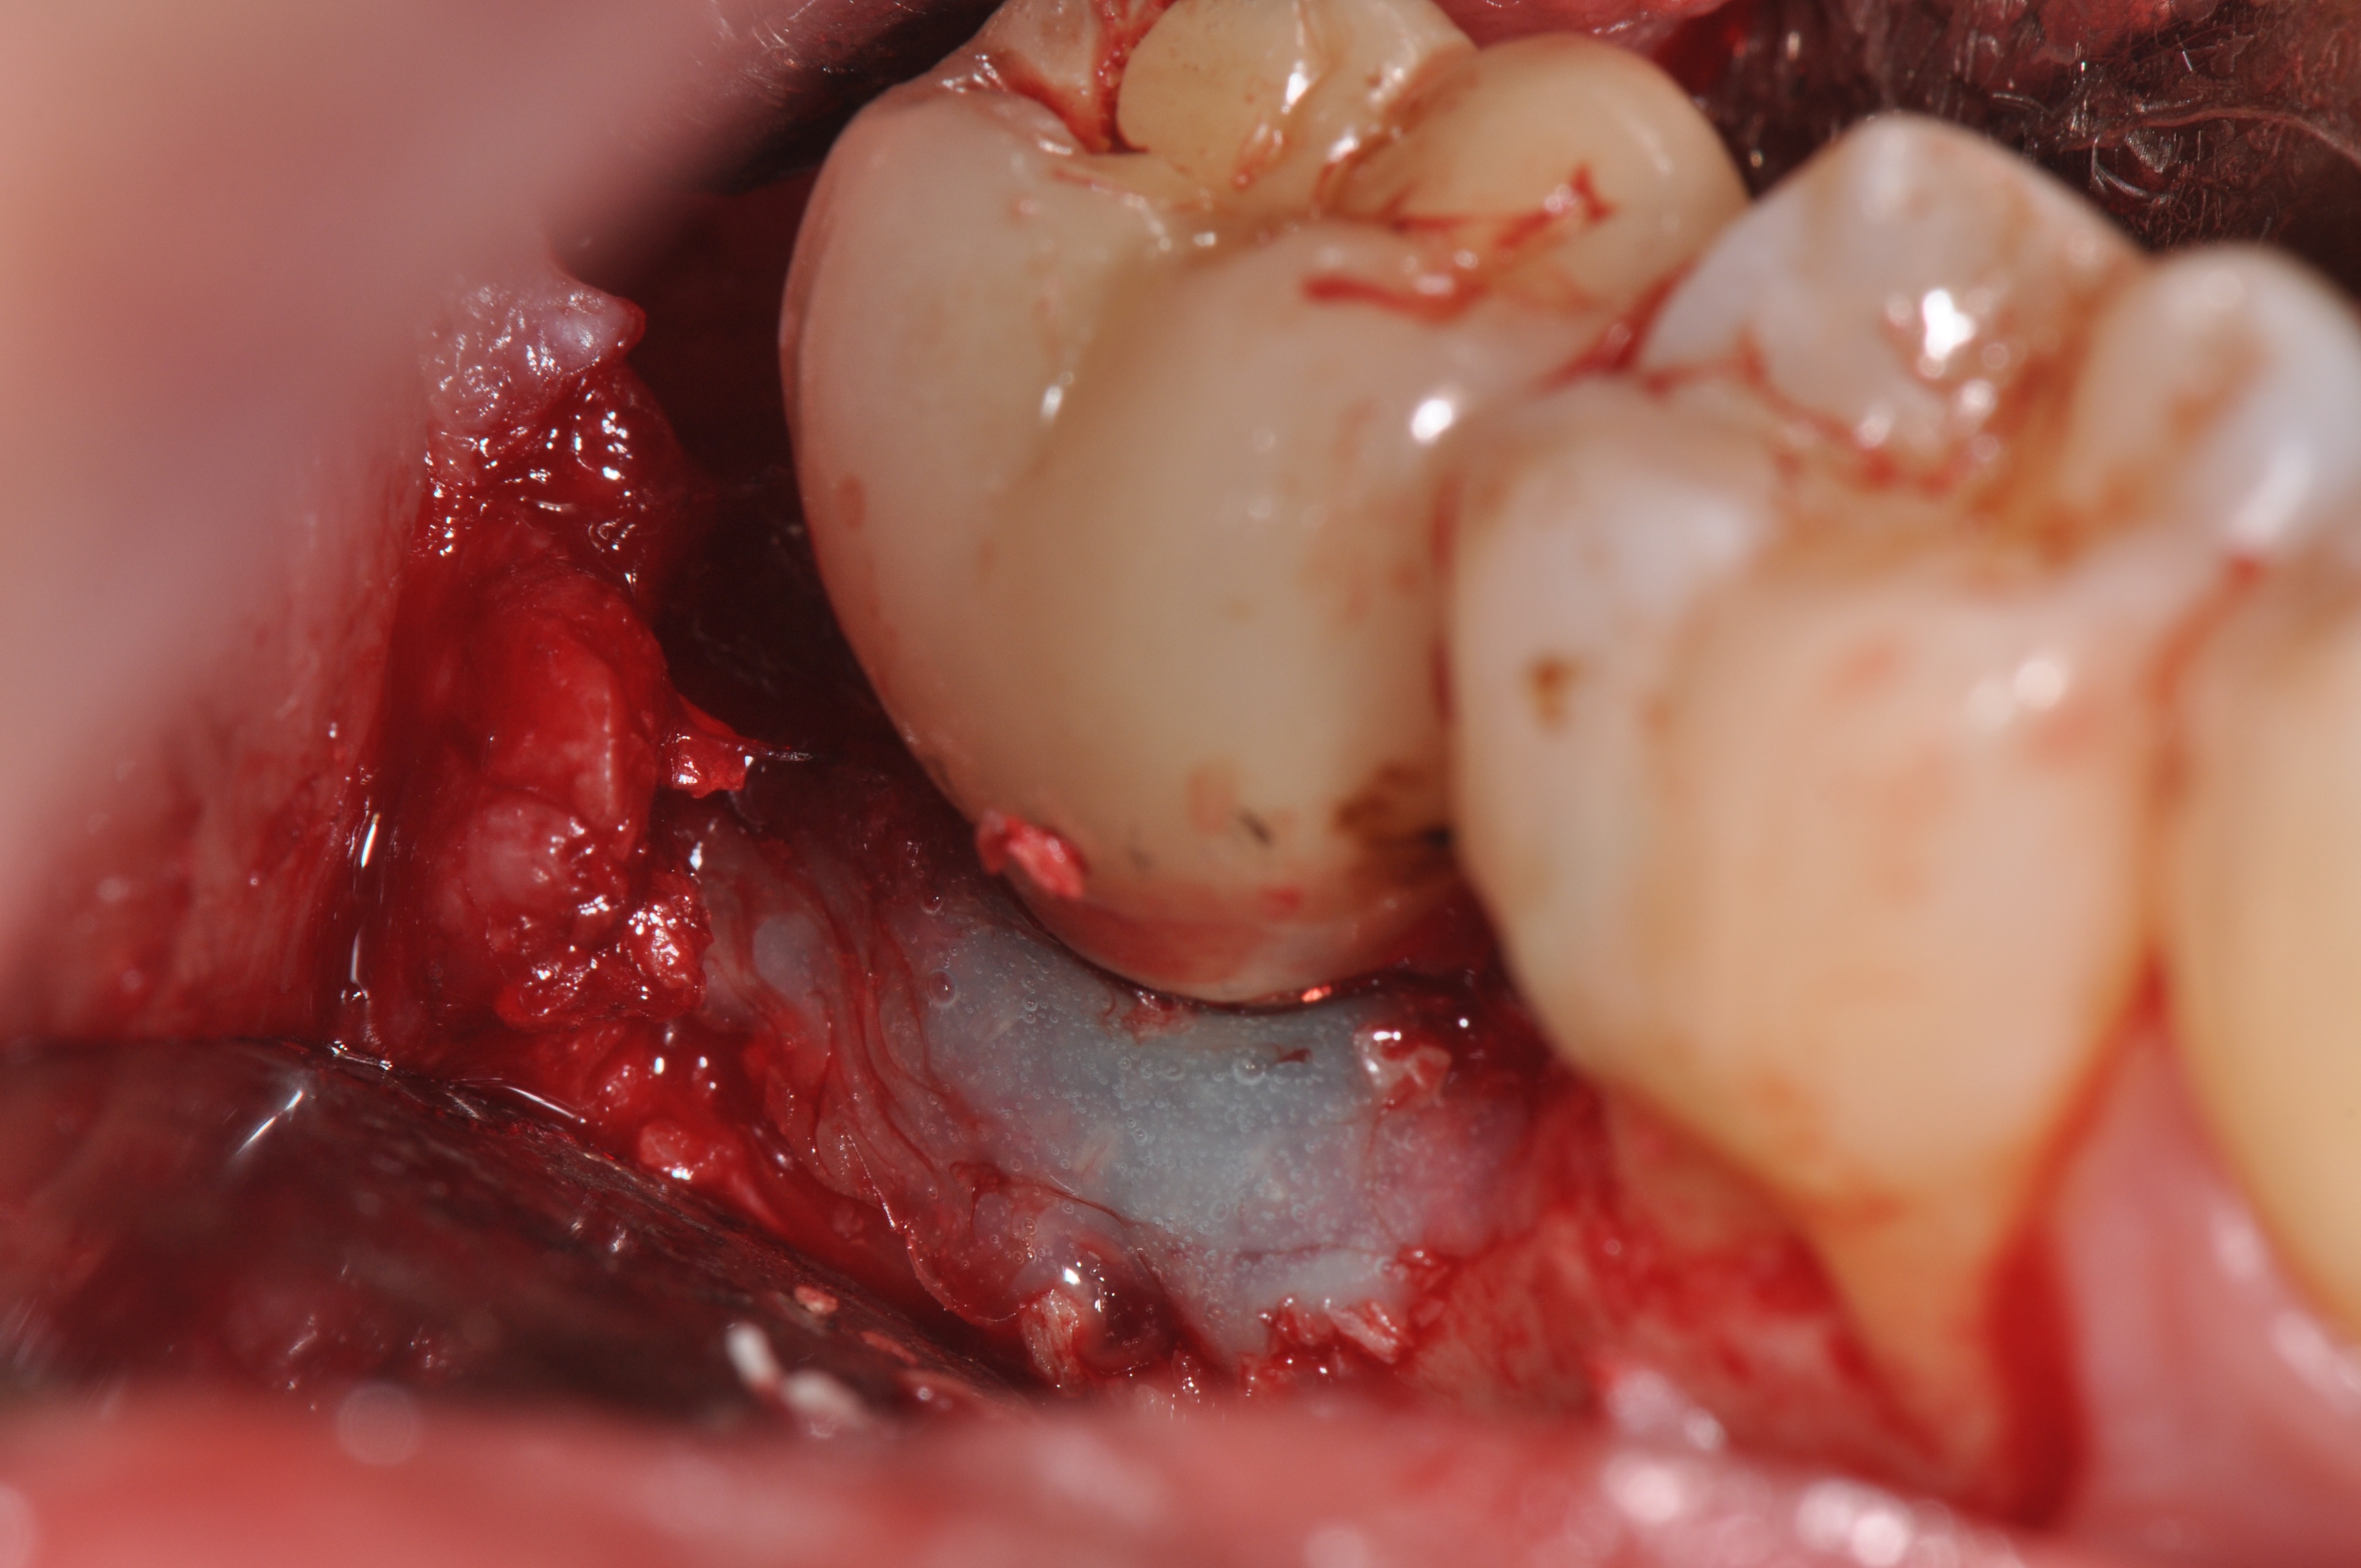

Pretreatment radiograph of a peri-implantitis

lesion on a 51-year-old male patient with a noncontributory medical history. The implant had been placed 3 years prior and presented with 8 mm pocketing with purulence.

Figure 1

Clinical exposure of a circumferential lesion that demonstrates 3 mm of bone loss. No cement was present, suggesting that the lesion was of bacterial origin. Surface decontamination included citric acid.

Figure 2